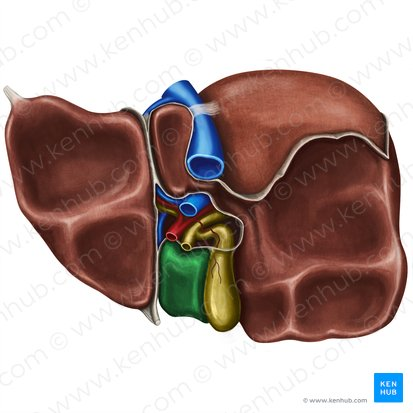

Quadrate Lobe

A small, quadrilateral lobe of the liver located inferiorly and medially on the visceral surface, bordered by the gallbladder and the fissure for the round ligament.

Caudate Lobe

A small lobe of the liver located posteriorly on the visceral surface, near the inferior vena cava and the fissure for the ligamentum venosum.

Gallbladder

A small, pear-shaped organ located beneath the liver that stores and concentrates bile produced by the liver.

Right Hepatic Duct

A duct that carries bile produced by the right lobe of the liver.

Left Hepatic Duct

A duct that carries bile produced by the left lobe of the liver.

Common Hepatic Duct

The duct formed by the union of the right and left hepatic ducts, which carries bile away from the liver.

Cystic Duct

The duct that connects the gallbladder to the common hepatic duct, allowing bile to enter and exit the gallbladder.

Hepatic Artery

A branch of the celiac artery that supplies oxygenated blood to the liver.

Hepatic Portal Vein

A large vein that carries deoxygenated but nutrient-rich blood from the digestive organs (stomach, intestines, spleen, pancreas) to the liver for processing.

Inferior Vena Cava

A large vein that carries deoxygenated blood from the lower and middle body back to the heart.